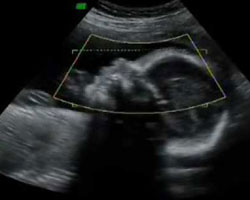

Queres ver como é um bebé na semana da gravidez em que estás? E queres vê-lo em movimento? Pois aqui tens um vídeo e uma ecografia que te vão dar uma ideia bastante aproximada!

Ecografia de 27 semanas